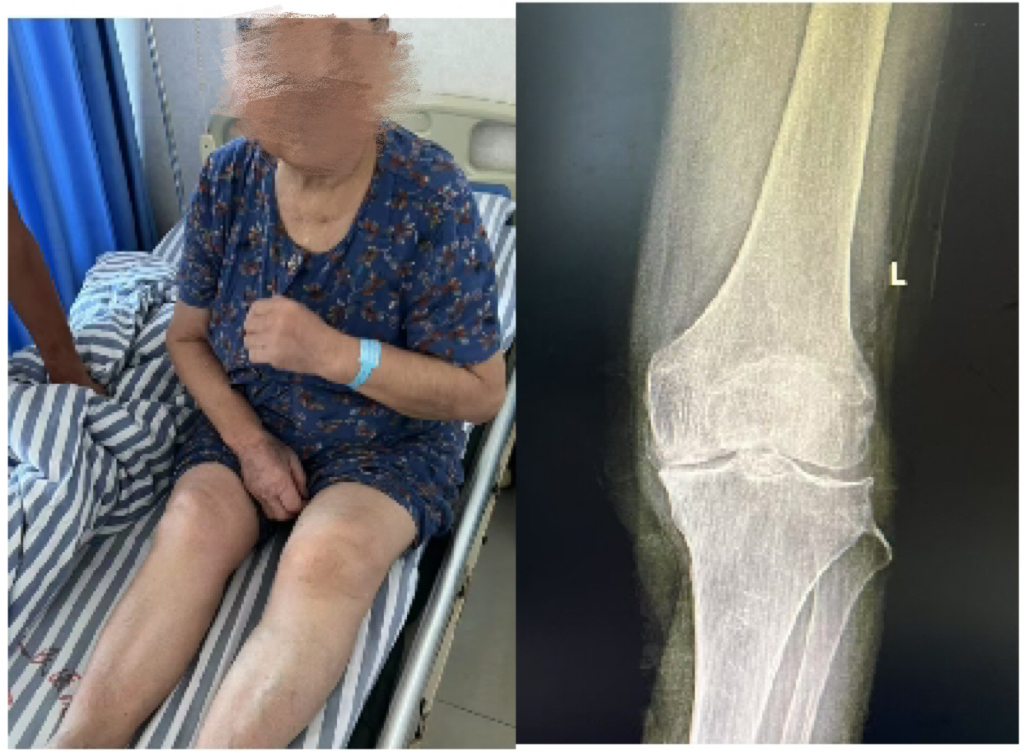

患者邹奶奶,女,79岁,因左膝严重疼痛并伴有明显活动受限,严重影响日常生活,来沅江市人民医院就诊。经影像学检查,显示其左膝关节间隙显著狭窄、软骨严重磨损,并伴有内翻畸形,符合IV期骨性关节炎表现,具备明确手术指征。

【术前影像】